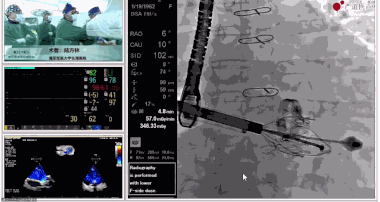

▲瓣膜植入前右心室造影

▲瓣膜植入過程

▲瓣膜植入后釋放的過程